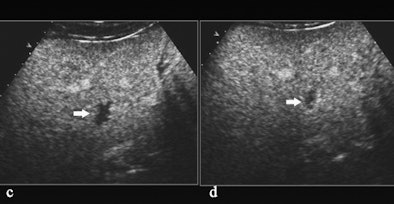

| Hemangioma with atypical enhancement on CT. (a) Contrast-enhanced CT, transverse plane. A solid lesion (arrow) appearing persistently hypovascular during the different dynamic phases (here represented during the portal-venous phase) is identified on the right liver. (b-d) Contrast-enhanced US after sulphur hexafluoride-filled microbubble injection during arterial (b), portal (c), and late phases (d). The lesion presents with globular peripheral enhancement during arterial phase (b), with a progressive centripetal fill-in during portal-venous (c) and late phase (d). Diagnosis of hemangioma was made after contrast-enhanced US. All images courtesy of Emilio Quaia, MD. |